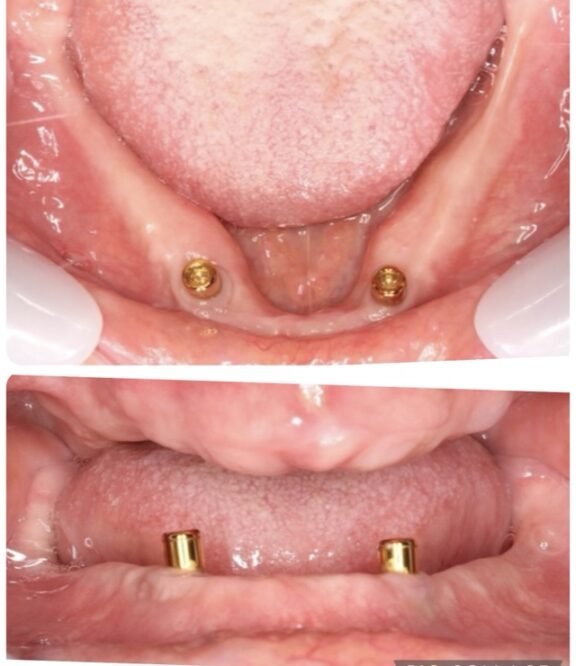

※インプラント(人工歯根)に

固定装置(ロケーターアバットメント)を取り付け、

義歯にも固定装置を取り付けました。